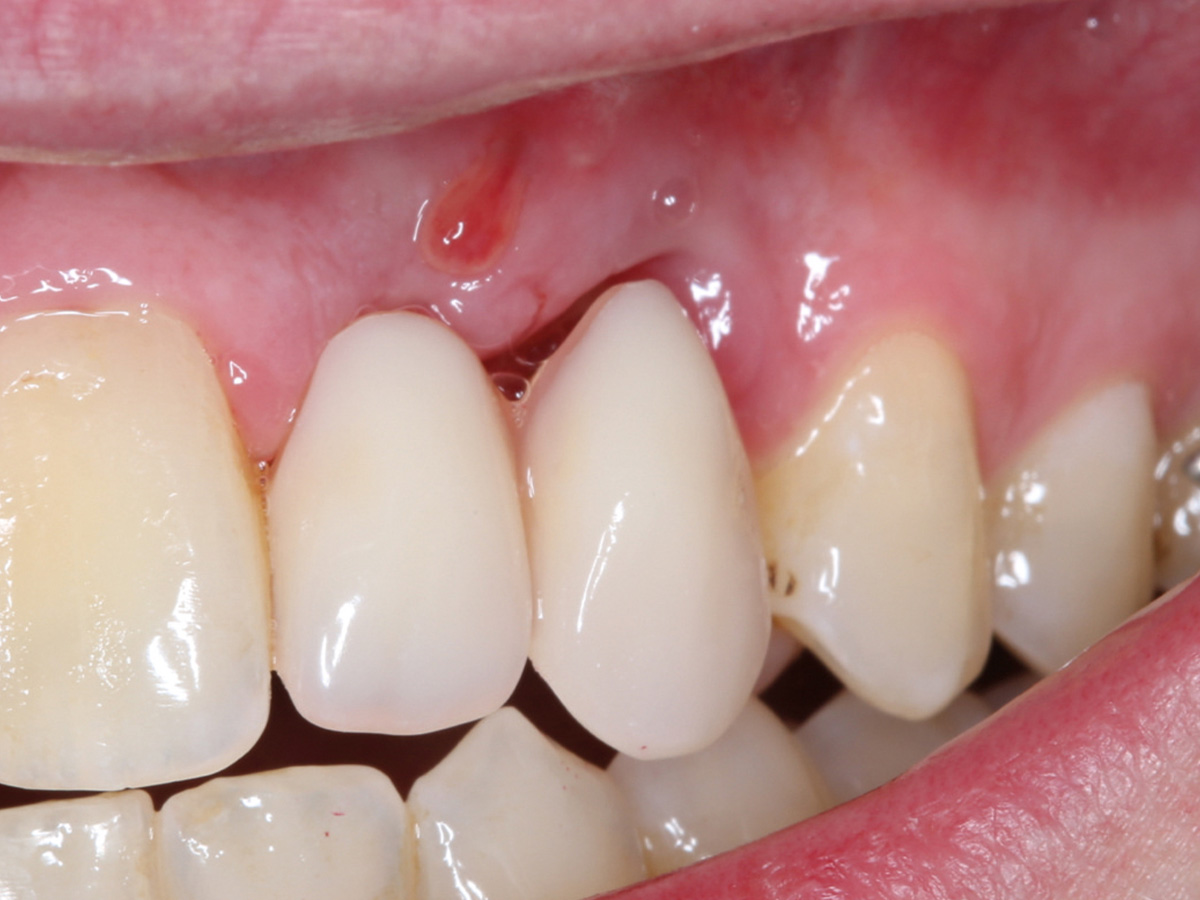

Abbildung 1

Klinische Ausgangssituation lateral, spontane Blutung.